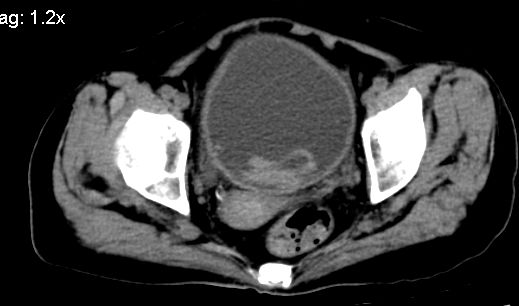

膀胱后壁见不规则致密影,我们遇到这样的病人都再做一次俯卧位扫描;排出膀胱内凝血块。

1.膀胱后壁见不规则致密影,占位?膀胱内凝血块?建议俯卧位扫描、膀胱镜检查.

膀胱三角区不规整软组织改变,双侧输尿管扩张,所以占位性病变肯定首先考虑,建议改变体位扫描除外游离血块影,但老年人出血原因一定要查明。

补充一下,谢谢提醒!

1.膀胱后壁见不规则致密影,随体位改变,为膀胱内凝血块;

2.双侧输尿管下段扩张,临床有血尿病史,建议进一步检查,找出血原因。